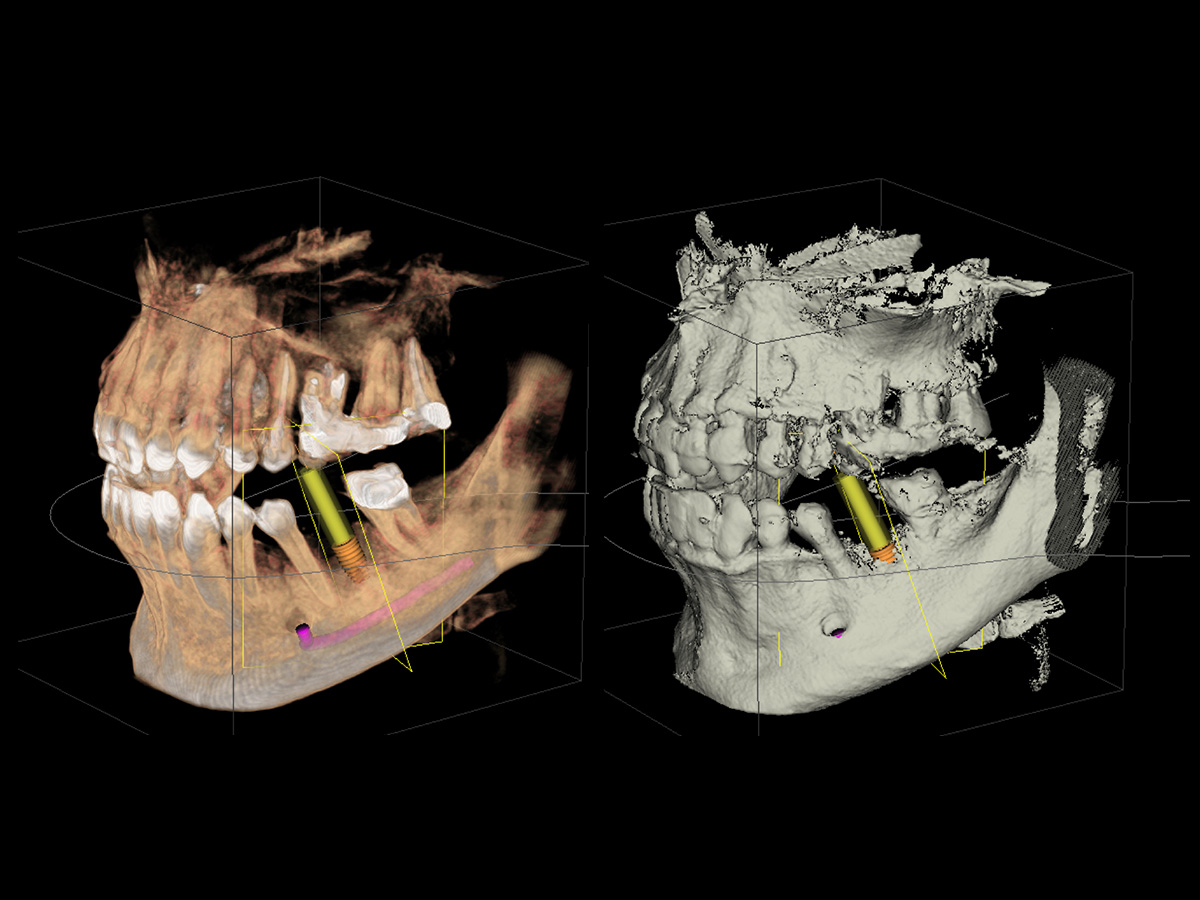

Bei diesem Fall handelt es sich um ein Standardproblem aus dem Patientenklientel von PD Dr. Michael Weinländer. Auf den DVT-Bildern ist ein fehlender Molar mit einer Atrophie der bukkalen Knochenwand zu sehen, was sowohl in der volumetrischen Darstellung (Abb. 1) als auch der Oberflächendarstellung (Abb. 2) gut zu erkennen ist.

Einen horizontalen Schnitt durch die entsprechende Knochenregion mit den gemessenen Knochenbreiten zeigt Abb. 3, während Abb. 4 die geplante Implantatgröße mit den Knochenbreiten im zervikalen Anteil des Kieferkammes abbildet.

Abbildung 1

Ausgangssituation (DVT-Bilder): Fehlender Molar mit Atrophie der bukkalen Knochenwand.

Abbildung 2

Horizontaler Schnitt durch die entsprechende Knochenregion und gemessene Knochenbreiten.

Abbildung 3

Geplante Implantatgröße mit Knochenbreiten im zervikalen Anteil des Kieferkammes.

Abbildung 4